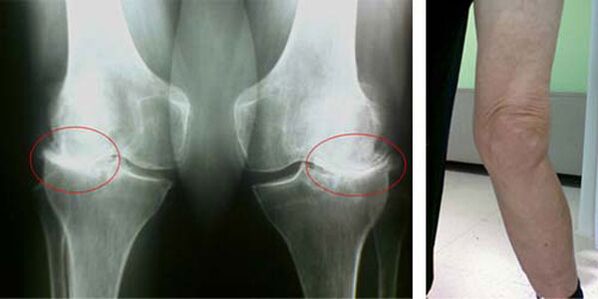

Etapele inițiale ale apariției unei astfel de patologii precum artroza articulației genunchiului nu se manifestă vizual în niciun fel. Cu toate acestea, după un anumit timp, pacientul observă semne de deformare a genunchiului, precum și o curbură caracteristică de-a lungul axei piciorului inferior (îndreptată spre interior). Există, de asemenea, o criză atunci când trebuie să îndoiți piciorul.

Prezența durerii, mișcarea limitată a genunchiului face ca o persoană să se prezinte la medic și să fie supusă unei examinări. Pentru a face acest lucru, trebuie să treacă teste și să facă o radiografie a articulației bolnave. Dacă aceste măsuri nu sunt suficiente pentru a confirma artroza articulației genunchiului, atunci se efectuează imagistica prin rezonanță magnetică. Pe baza datelor colectate, medicul alege cele mai bune metode de tratament.